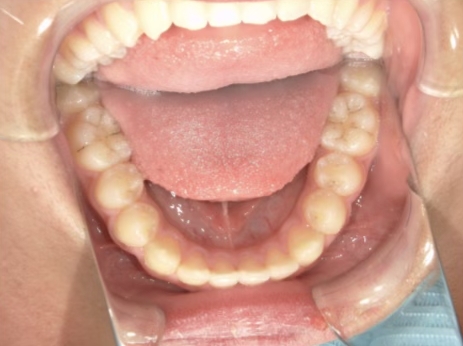

治療中⑨ 中3:14y4m

モノブロック装置で左上八重歯が改善しました

今後、必要によりマルチブラケット法へ移行予定です